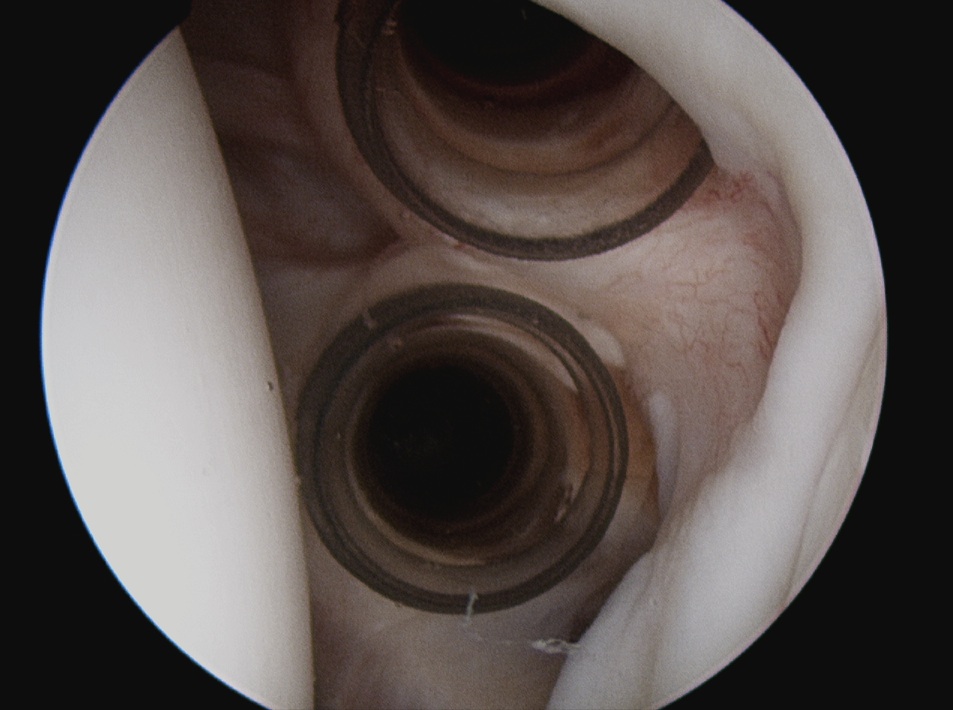

Shoulder Portals Labral RepairRotator Interval 2 cannulas

Posterior portal Anterosuperior portal Anteroinferior portal

Rotator interval at angle between biceps and glenoid

Inferior and lateral to Anterosuperior portal

Shoulder Arthroscopy Posterior Portals Shoulder Arthroscopy Anterosuperior Portal Shoulder Scope Anteroinferior Portal